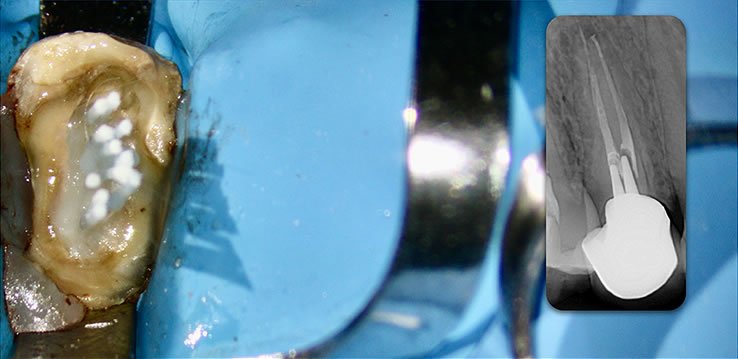

Retain 100% of remaining healthy tooth structure

- Biolight® DRILL-FREE adapts to all shaped canals, while conserving all remaining healthy tooth structure.

- There is no need to drill out portions of canals to accommodate post spaces.

- Easily place multi-posts in multiple canals as the post bends with the natural canal shape.